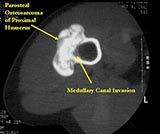

- Parosteal osteosarcomas that are present for prolonged periods of time may either have areas that become higher grade or dedifferentiate. Dedifferentiation refers to a portion of the tumor changing and becoming a high grade type of sarcoma. In addition, parosteal osteosarcomas that are present for a prolonged period of time can invade the bone (medullary canal) that it arose from. Tumors that have undergone dedifferentiation or invaded the underlying bone are more aggressive and have a higher risk of metastasizing (spreading). This is important to know for treatment purposes. Typically, low grade parosteal osteosarcomas are treated with surgery alone. Parosteal osteosarcomas with high grade areas may also be treated with chemotherapy in addition to surgery.

- Proximal humerus (15%); Tibia (10%); Fibula (3%), Radius, Ulna

- There may be invasion of the medullary canal with long standing disease

- Useful for determining medullary invasion

- Can help discern areas that may be high grade

- Most useful for evaluating the local extent of the tumor and relationship to neurovascular structures the circumference of the femur involved by the tumor (important for surgical planning)

- If it has grown through the cortex, there may be an intramedullary component

- Metastases more common with medullary invasion, high grade components (grade 3) and dedifferentiation (grade 3 tumors)

- Many parosteal osteosarcomas with intramedullary extension are higher grade lesions or dedifferentiated tumors